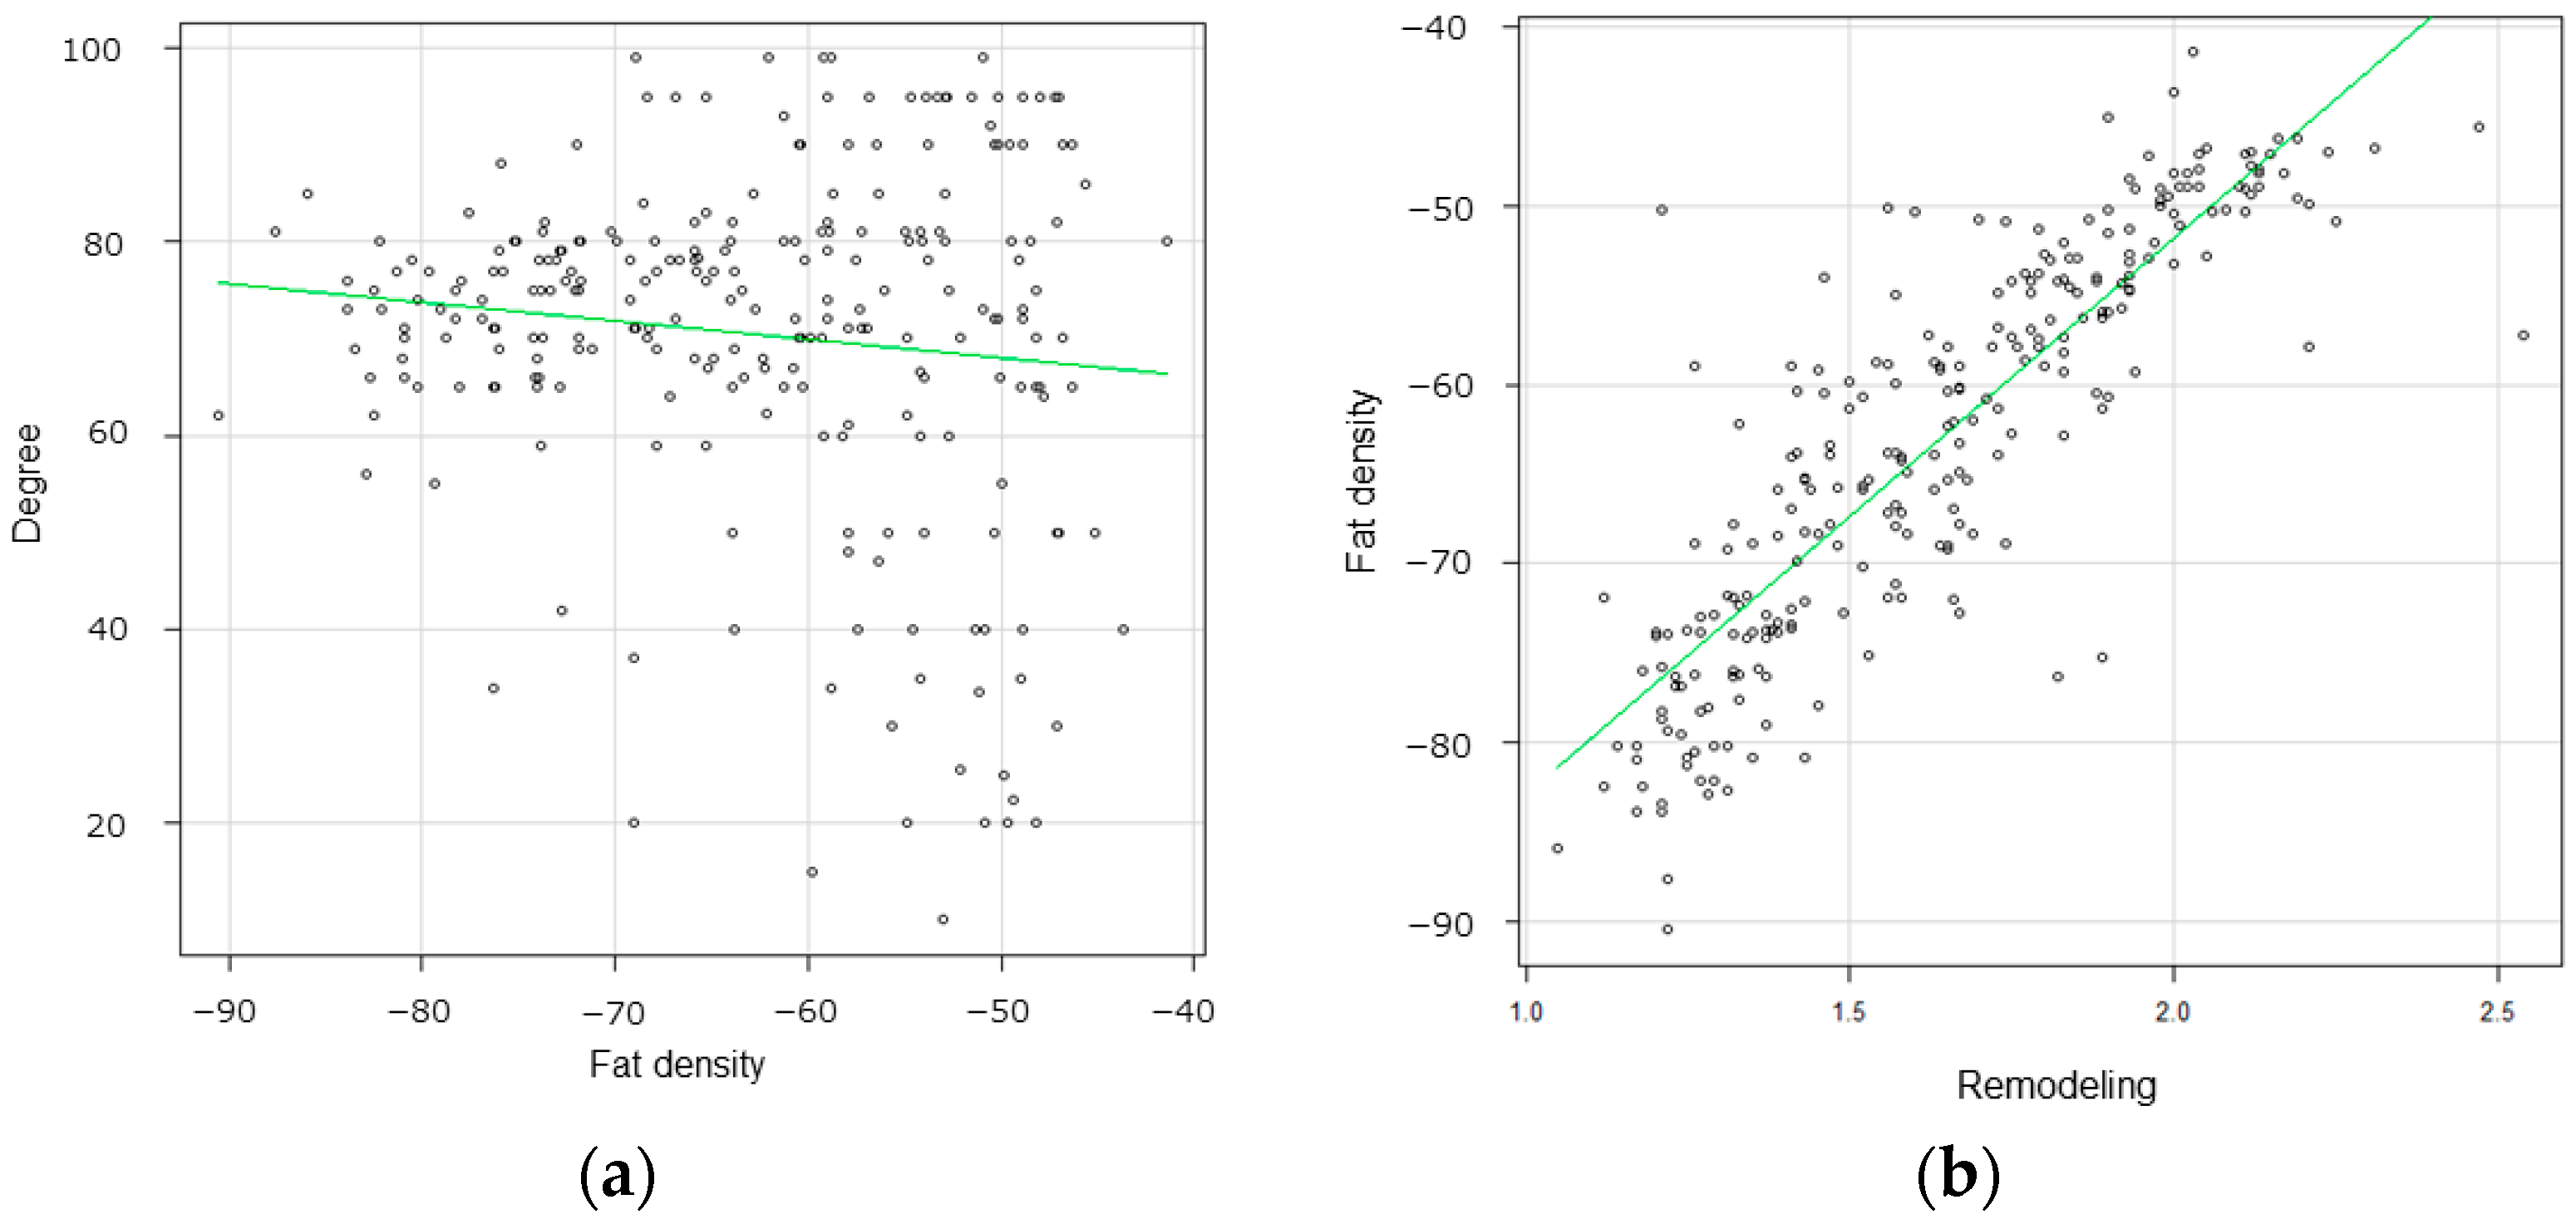

3.2. Radiological Findings

3.3. Correlation between Pericarotid Fat Density and IHC